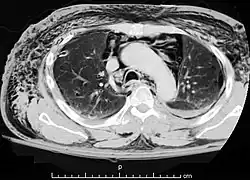

A CT scan showing air in the mediastinum with subcutaneous emphysema, which can result in Hamman's syndrome

Hamman's syndrome, also known as Macklin's syndrome, is a syndrome of spontaneous subcutaneous emphysema[1] (air in the subcutaneous tissues of the skin) and pneumomediastinum (air in the mediastinum, the center of the chest cavity), sometimes associated with pain and, less commonly, dyspnea (difficulty breathing), dysphonia, and a low-grade fever.